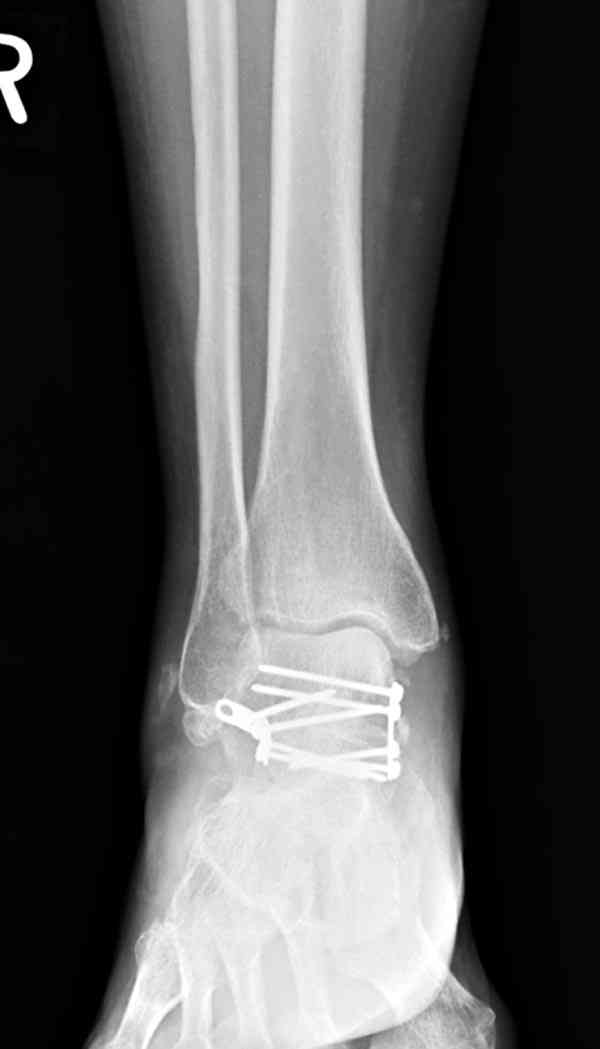

Случай с множественным оскольчатым переломом тарана оперированный из двойного доступа.

Через 14 мес.:

(кстати, на нашем случае была применена костная пластика-allograft crouton для заполнения дефектов)